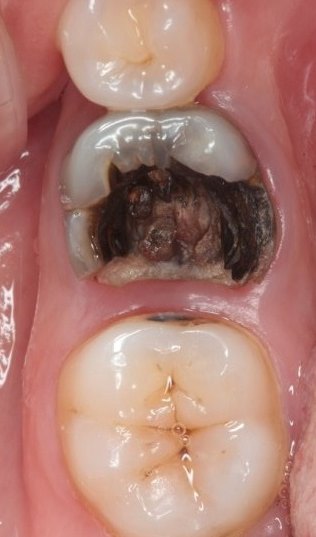

医生检查发现溃疡处对应的牙床上有一颗蛀牙,她回忆嘴里的这颗蛀牙有好多年了,开始时蛀了一个洞,慢慢牙冠蛀没了,只留下牙根和露在外面的一点点残牙,由于不疼不痒,她也就没有拔掉。而这颗坏牙正是导致口腔癌的罪魁祸首。由于蛀残牙十分锋利,吃东西时,很容易戳到口腔黏膜,在这种长期的刺激下,就易发生癌变。

与机械性刺激、化学性灼伤或者热冷刺激有密切关系,其发病部位和形态与机械刺激因子相符合。无复发史,去除刺激后溃疡很快愈合;但如果任其发展,则有癌变可能。

4.癌性溃疡

多为其他溃疡恶变而来。老年人多见,也见于青少年。近年有低龄化趋势。形态多不规则,其边缘隆起呈凹凸不平状,与周围组织分界不清,溃疡面的基底部不平整,呈颗粒状,触之硬韧,和正常黏膜有明显的区别,疼痛不明显。恶性溃疡病程长,数月甚至一年多都不愈合或逐渐扩大,常规消炎防腐类药物治疗效果不明显。良性口腔溃疡患者较少出现全身症状;恶性口腔溃疡患者则相反,可出现发热、颈部淋巴结肿大、食欲不振、消瘦、贫血、乏力等表现。